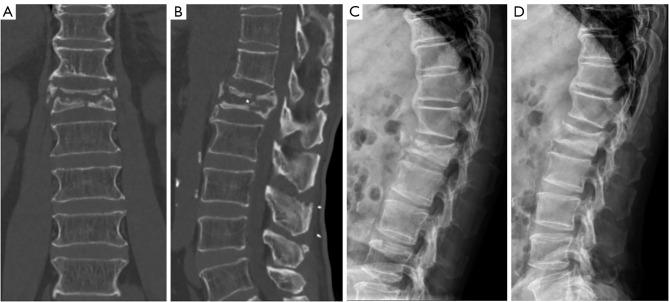

Kümmell's disease (KD), delayed post-traumatic vertebral collapse, is diagnosed with characteristic radiologic findings such as intravertebral vacuum cleft (IVC). Because patients with KD are elderly, have many underlying diseases, poor bone quality, and relatively limited surgical outcomes compared to other spinal diseases. The aim of this study is to describe a minimally invasive surgical technique and to evaluate the clinical and radiological outcomes of this technique.

As a surgical treatment method for KD, we performed bone substitute packing via small pedicle holes with a posterior instrumented fusion. Ten consecutive patients underwent surgery for KD. Clinical outcomes and radiologic parameters were evaluated pre- and post-operatively.